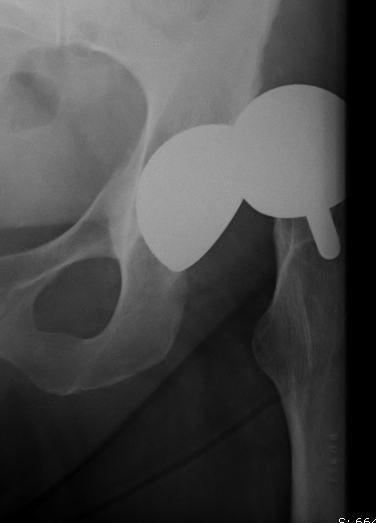

Birmingham hip resurfacing

Aseptic loosening

Issue

- cannot revise to metal on metal

- need to revision acetabular component as well

- revision of 53 hip resurfacing

- 10 year survival 63%

- worse outcomes with revision of metallosis

- worse outcomes with femoral revision only to MoM bearing

- Australian Joint Registry of 884 resurfacings undergoing revivision

- 10% re-revision rate of 26%